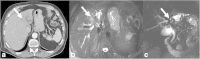

Malignancies of the biliary tract include cholangiocarcinoma, gallbladder cancers and carcinoma of the ampulla of Vater. Biliary tract adenocarcinomas are the second most common primary hepatobiliary cancer. Due to their slow growing nature, non-specific and late symptomatology, these malignancies are often diagnosed in advanced stages with poor prognosis. Apart from incidental discovery of gall bladder carcinoma upon cholecystectomy, early stage biliary tract cancers are now detected with computed tomography (CT) and magnetic resonance imaging (MRI) with magnetic resonance cholangiopancreatography (MRCP). Accurate characterization and staging of these indolent cancers will determine outcome as majority of the patients' are inoperable at the time of presentation. Ultrasound is useful for initial evaluation of the biliary tract and gallbladder masses and in determining the next suitable modality for further evaluation. Multimodality imaging plays an integral role in the management of the biliary tract malignancies. The imaging techniques most useful are MRI with MRCP, endoscopic retrograde cholangiopancreatography (ERCP), endoscopic ultrasound (EUS) and positron emission tomography (PET). In this review we will discuss epidemiology and the role of imaging in detection, characterization and management of the biliary tract malignancies under the three broad categories of cholangiocarcinomas (intra- and extrahepatic), gallbladder cancers and ampullary carcinomas.